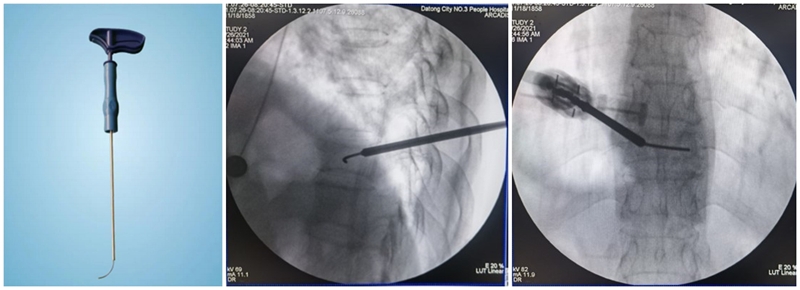

(2)弯角导丝开腔:弯角骨钻开腔器械刺入椎体时,注意开腔工具手柄与伤椎终板平行,不要强行开腔,多透视侧位,否则弯导丝可能穿破终板,导致医源性骨水泥渗漏。C形臂X线机正位透视下,导丝到达椎体对侧椎弓根处即可。

(3)弯角骨钻扩张:C形臂X线机正位透视下,弯角骨钻开腔器械螺旋手柄顺时针扭转,让弯角骨钻沿导丝前进开路,将椎体内部钻出弧形通道。操作中注意骨钻沿导丝旋进旋出要完全,旋进不够,后期球囊无法到达对侧,旋出不完全,骨钻会卡在工作套筒上无法拔出。